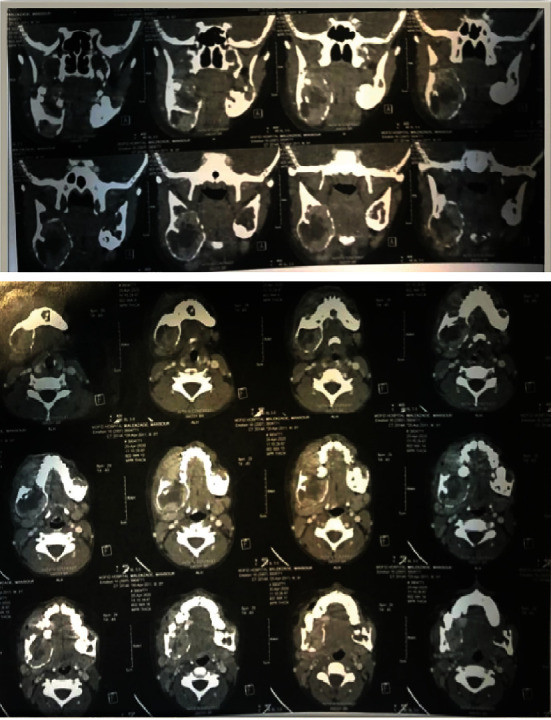

Central giant cell granuloma (CGCG) is considered a benign intraosseous lesion with a varied range of clinical features in two subtypes, including aggressive and non-aggressive lesions. This study presents a 9-year-old boy with multiple bilateral CGCG in the mandible without any systemic disease or specific syndrome. Clinical, radiographic, and histopathological findings demonstrated the aggressive lesions. It is discussed how the differential diagnosis and treatment can be determined based on the patient's age as well as the size and manner of the lesion.

Abstract Image